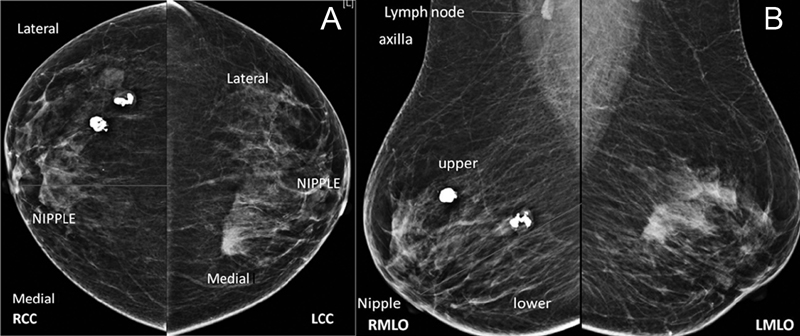

Mammograms are routinely performed in two views, cranio-caudal view and medio-lateral oblique view). These views are not orthogonal to each other but are obtained to evaluate the maximum of breast parenchyma. Once the abnormality is detected on one view of the breast, we need to localize in the other view to predict its location in the breast ([Fig. 4A] and [B]). This is not so important for palpable abnormality but of extreme importance in non-palpable abnormality. Once we localize the abnormality on mammograms, we can evaluate it further with additional views on mammograms if needed or/and with US.

| Figure.4:(A and B): Right and left breast mammograms in CC and MLO views. On the right side, popcorn calcifications of involuting fibroadenoma are seen in the outer region on the CC view and in the upper region in the MLO view on the right side. So, they are located in the upper outer quadrant in the right breast, whereas ill-defined high-density mass on the left side is located in the upper inner quadrant. CC, craniocaudal; CEM, contrast-enhanced

| Figure.4:(A and B): Right and left breast mammograms in CC and MLO views. On the right side, popcorn calcifications of involuting fibroadenoma are seen in the outer region on the CC view and in the upper region in the MLO view on the right side. So, they are located in the upper outer quadrant in the right breast, whereas ill-defined high-density mass on the left side is located in the upper inner quadrant. CC, craniocaudal; CEM, contrast-enhanced